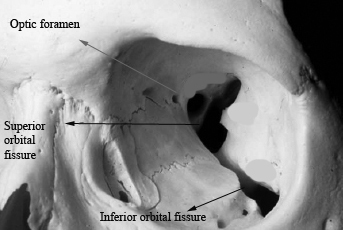

Superior orbital fissure: is a linear notch between the greater and lesser wings of sphenoid. The superior portion of the fissure is narrower and here the lacrimal, frontal and trochlear nerves passes through outside the annulus of zinn. The annulus of zinn is a ring of fibrous tissue surrounding the optic nerve at its entrance into the apex of orbit. This ring gives origin to the extra ocular muscles. The following structures pass through the superior orbital fissure within the annulus of zinn:

1. Superior and inferior divisions of oculomotor nerve

2. The abducent nerve

3. Naso ciliary branch of ophthalmic branch of trigeminal nerve

4. Major venous orbital drainage exit via the superior orbital fissure to drain into the cavernous sinus.

Medial to the superior orbital fissure is the optic foramen through which the optic nerve passes. This formen which is present in the lesser wing of sphenoid also conveys the ophthalmic artery. The optic foramen and optic canal are separated from the superior orbital fissure by a bony optic strut. In adults the optic canal is 8 - 10 mm long and 5 - 7 mm wide. The optic foramen is about 6.5 mm in diameter. The optic canal is known to attain its full adult size by the age of 3. The optic foramen on both sides are universally symetrical. Any variation in size even to the extent of 1mm should be considered as pathological.

Superior orbital fissure

The inferior orbital fissure lies between the lateral orbital wall and the floor of the orbit. It is about 20 mm long. The following structures pass through this fissure:

1. Maxillary division of trigeminal nerve

2. Zygomatic nerve

3. Branches from the sphenopalatine ganglion

4. Branches of inferior ophthalmic vein leading on to pterygoid plexus.